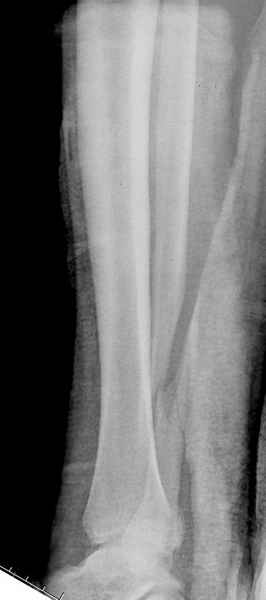

Импрессия медиальной части суставной поверхности бывает при супинационном механизме перелома лодыжек (тип А по классификации АО). Здесь механизм пронациия+наружная ротация (тип С, синдесмоз и межкостная мебрана повреждены),

перелом медиальной лодыжки отрывной, при этом в 20-30% бывает повреждение дельтовидной связки.

Клиновидность щели сустава следствие повреждения дельты, невосстановления длины малоберцовой или (хотел сказать "установки в гипсе", но оного, вроде,

нет)? Устранить бы причину. А равно как и тенденцию" к наружному подвывиху. Чрескостный остеосинтез - метод выбора.

Перелом типа Вебер С с эверсионным механизмом травмы всегда сопровождается повреждением дистального межберцового синдезмоза, поэтому вместе с фиксацией переломов лодыжек( малоберцовой кости) автоматом выполняется фиксация синдесмоза винтом, который обычно удаляется через 8 недель -

При реконструкции голеностопа, о важности восстановления длины малоберцовой для профилактики пост травматического артроза разбирали в предыдущих дискуссиях. Нарушенную биомеханику голеностопа без восстановления длины малоберцовой, не восстановить только швом медиальной связки.

Здесь похожий случай трехнедельной давности, перелом почти сросся и была укорочена малоберцовая, на операции длину малоберцовой смогли восстановить только после того, когда проксимальнее пластины ввели шуруп и использовали его как толкатель, с помощбю дистракционого инструмента (lamina spreader).

Меньше всего волнует положение медиальной лодыжки - в любое время можно провести остео или реостеосинтез, при несращении можно просто резецировать без ущерба для движений в голеностопе. Здесь обошлись фиксацией одним 4 мм канюлированным шурупом.